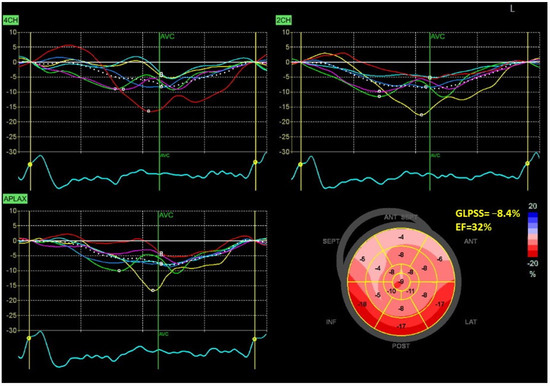

Figure 1 and Figure 2 show two contrasting examples (a healthy person and a patient after myocardial infarction and left bundle branch block) of STE curves with GLPSS, LVEF and LV pressure–strain loops and results of GWE for all LV segments.

Figure 2.

An example of echocardiography of a 61-year-old man with the left bundle branch block and a history of myocardial infarction. A set of individual longitudinal strain curves for all segments shown in different colors, with the average curve shown as a white dotted line, a bull’s eye of segmental longitudinal peak systolic strains and a summary of global longitudinal peak systolic strain (GLPSS) are shown in the top panel. The LV pressure–strain loop with the bull’s eye representation of myocardial work efficiency for each of the segments and a summary of all myocardial work indices are shown in the lower panel. Abbreviations: GLS—global longitudinal peak systolic strain, EF—ejection fraction, GWI—global myocardial work index, GCW—global constructive work, GWW—global wasted work, GWE—global work efficiency, BP—blood pressure.